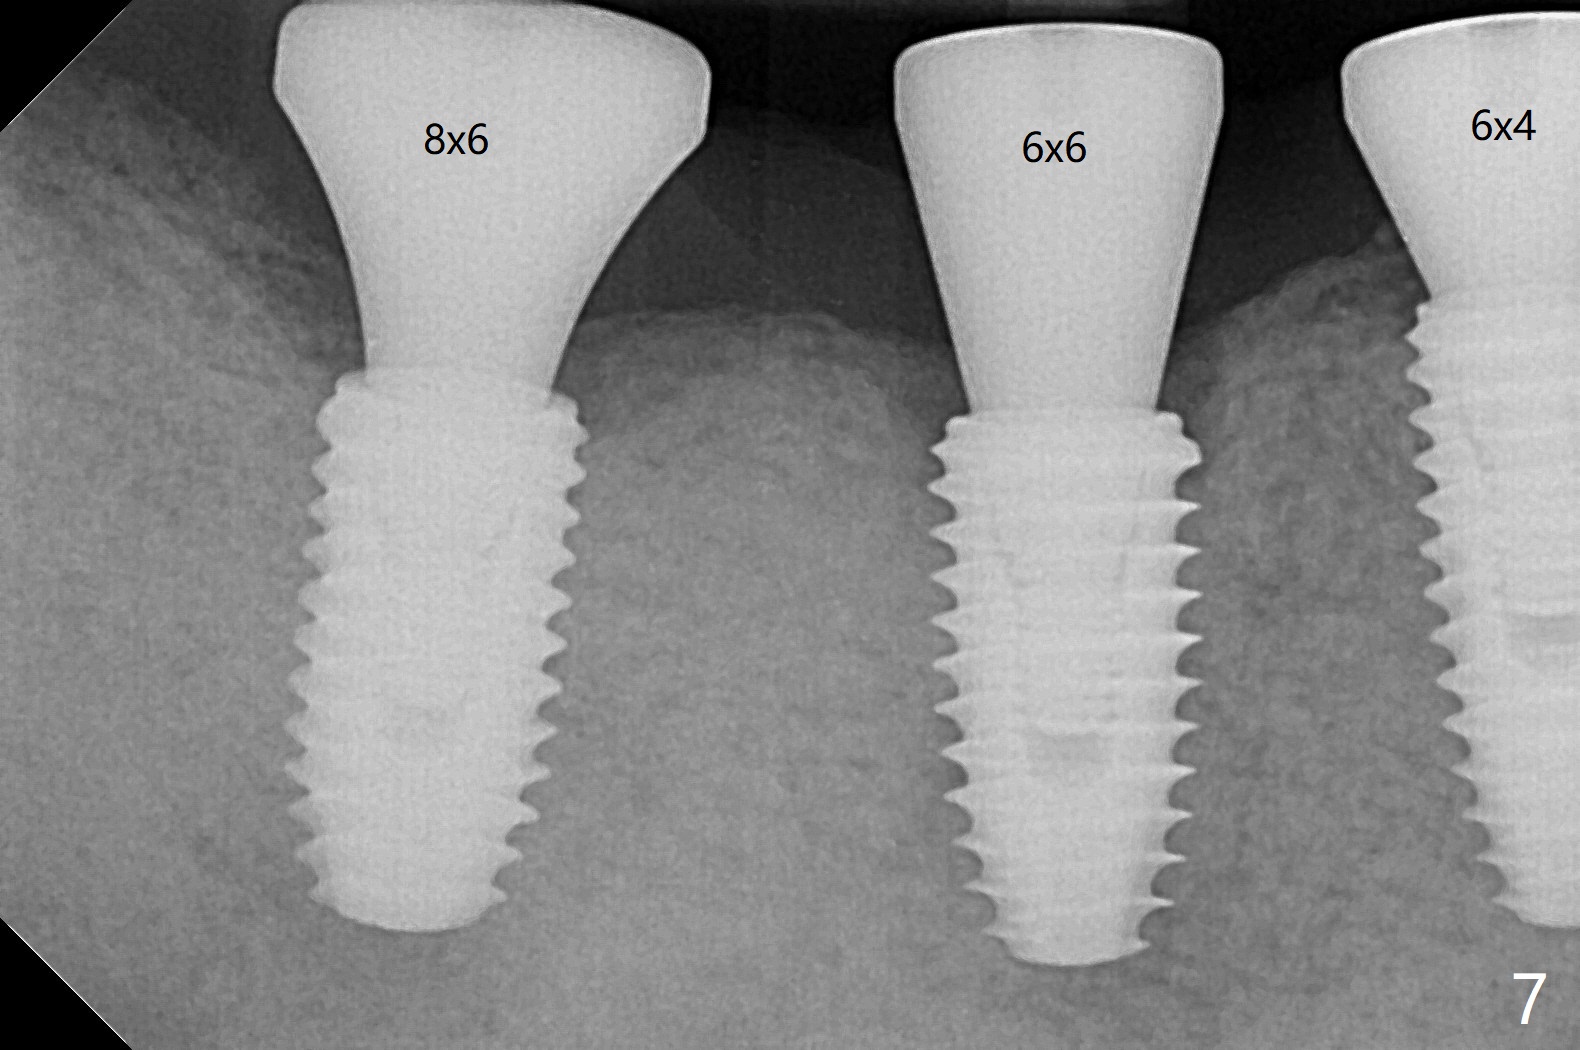

Five months post #31 implant removal with bone graft, osteotomy is initiated for a 5x10 mm implant using an existing guide. A question arises suddenly whether the bone height is reduced. Therefore a 4.5x10 mm dummy implant is placed with a fixture anchor placed at #30 (Fig.1 A). After using 4.5x8.5 mm drill with regular offset, a 5x10 mm definitive implant is placed with ~ 35 Ncm (Fig.2,3). After placement of the implant .5 mm deeper, a 8x6 mm healing abutment is placed, while the abutments return to #29 and 30 for splinted provisional (Fig.4). Two months later, the cemented abutment at #29 is loose (Fig.5) and retightened, but it remains incompletely seated for another 3 months (Fig.6). So is the one at #31 (Fig.6). After use of 4.6 and 5.6 mm bone profile drills, healing abutments are placed with apparently complete seating (Fig.7,8).